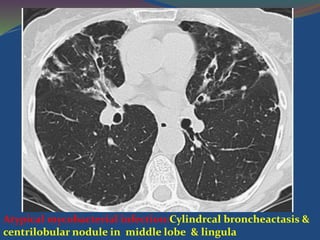

Atypical mycobacterial infection:Cylindrcal broncheactasis &

centrilobular nodule in middle lobe & lingula

Atypical mycobacterial infection:Cylindrcalbroncheactasis & centrilobular nodule in middle lobe & lingula